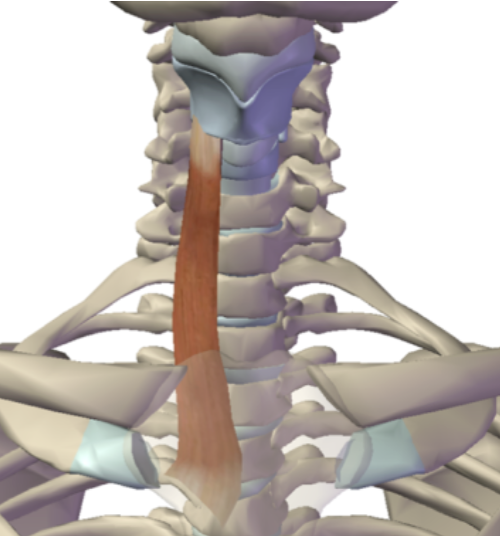

What is this muscle?

Sternothyroid (depress thyroid)